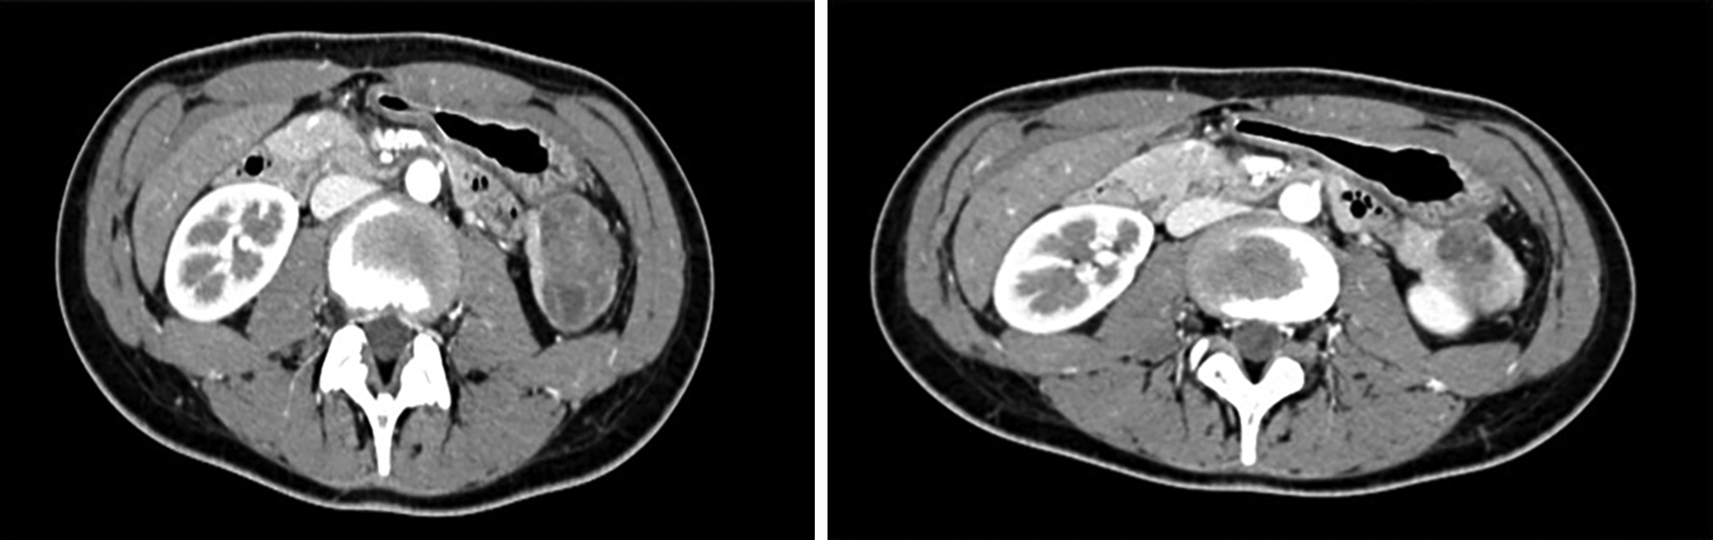

The physical examination was uneventful except for a tenderness at the level of the epigastrium. Laboratory findings were normal. The abdominal Doppler ultrasound showed a round, well limited solid vascular mass. It was actually a large one measuring 42 mm and extending from the retroperitoneum down to the lower pole of the homolateral kidney. It was hyperechogenic and heterogeneous in appearance but mostly cystic in nature. A computed tomography (CT) Scan of the abdomen and the pelvis together with a pancreatic MRI revealed the presence of a 44×42×34 mm solid mass in the pancreatic tail. This mass was spontaneously isodense with a moderate and heterogeneous contrast enhancement and some scattered cysts. This mass presented regular contours with a predominantly lower extension reaching the descending colon without any symptoms of compression. The peritoneal fat was of normal appearance (Figure 1). The biological, hepatic and pancreatic check-up was normal. The patient underwent operation. The surgical operation confirmed the existence of a large exophytic tumor (diameter: 5cm) appended to the lower edge of the pancreatic tail. There was no locoregional invasion or distant metastasis. Surgical resection of the tumor by partially cutting the pancreas was performed. The surgery was without complication. The histological examination revealed a solid pseudopapillary tumor of the pancreas. Indeed, the cyto-architectural aspects confirmed our diagnosis. An immuno-histochemical study showed the existence of CD10 tumor cells. The patient developed well in the postoperative period, with normal US (three, 12 and 24 and 48 months) and CT scans (12, 24 and 48 months) and no evidence of residual disease.

Figure 1. Abdominal magnetic resonance imaging showing a heterogeneous mass repulsing below the left kidney.

An abdominal computed tomography (CT) shows a limited heterogeneous lesion that is rather hypodense. It is not very vascularized. It is also of mixed composition associating solid and cystic zones and is little or partially enhanced at the periphery after injection of the contrast agent. Signs of compression of the adjacent organs can be observed. The magnetic resonance imaging (MRI) shows a heterogeneous lesion with a hyper signal in T1 and T2. The capsule is often visible in the form of a hypo-intense border in T1.13,14